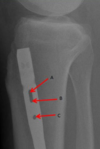

What supplies the inner and outer parts of bone? (blood vessels)

Nutrient artery system supplies inner 2/3

is a high pressure system

Periosteal system supplies outer 1/3

is a low pressure system